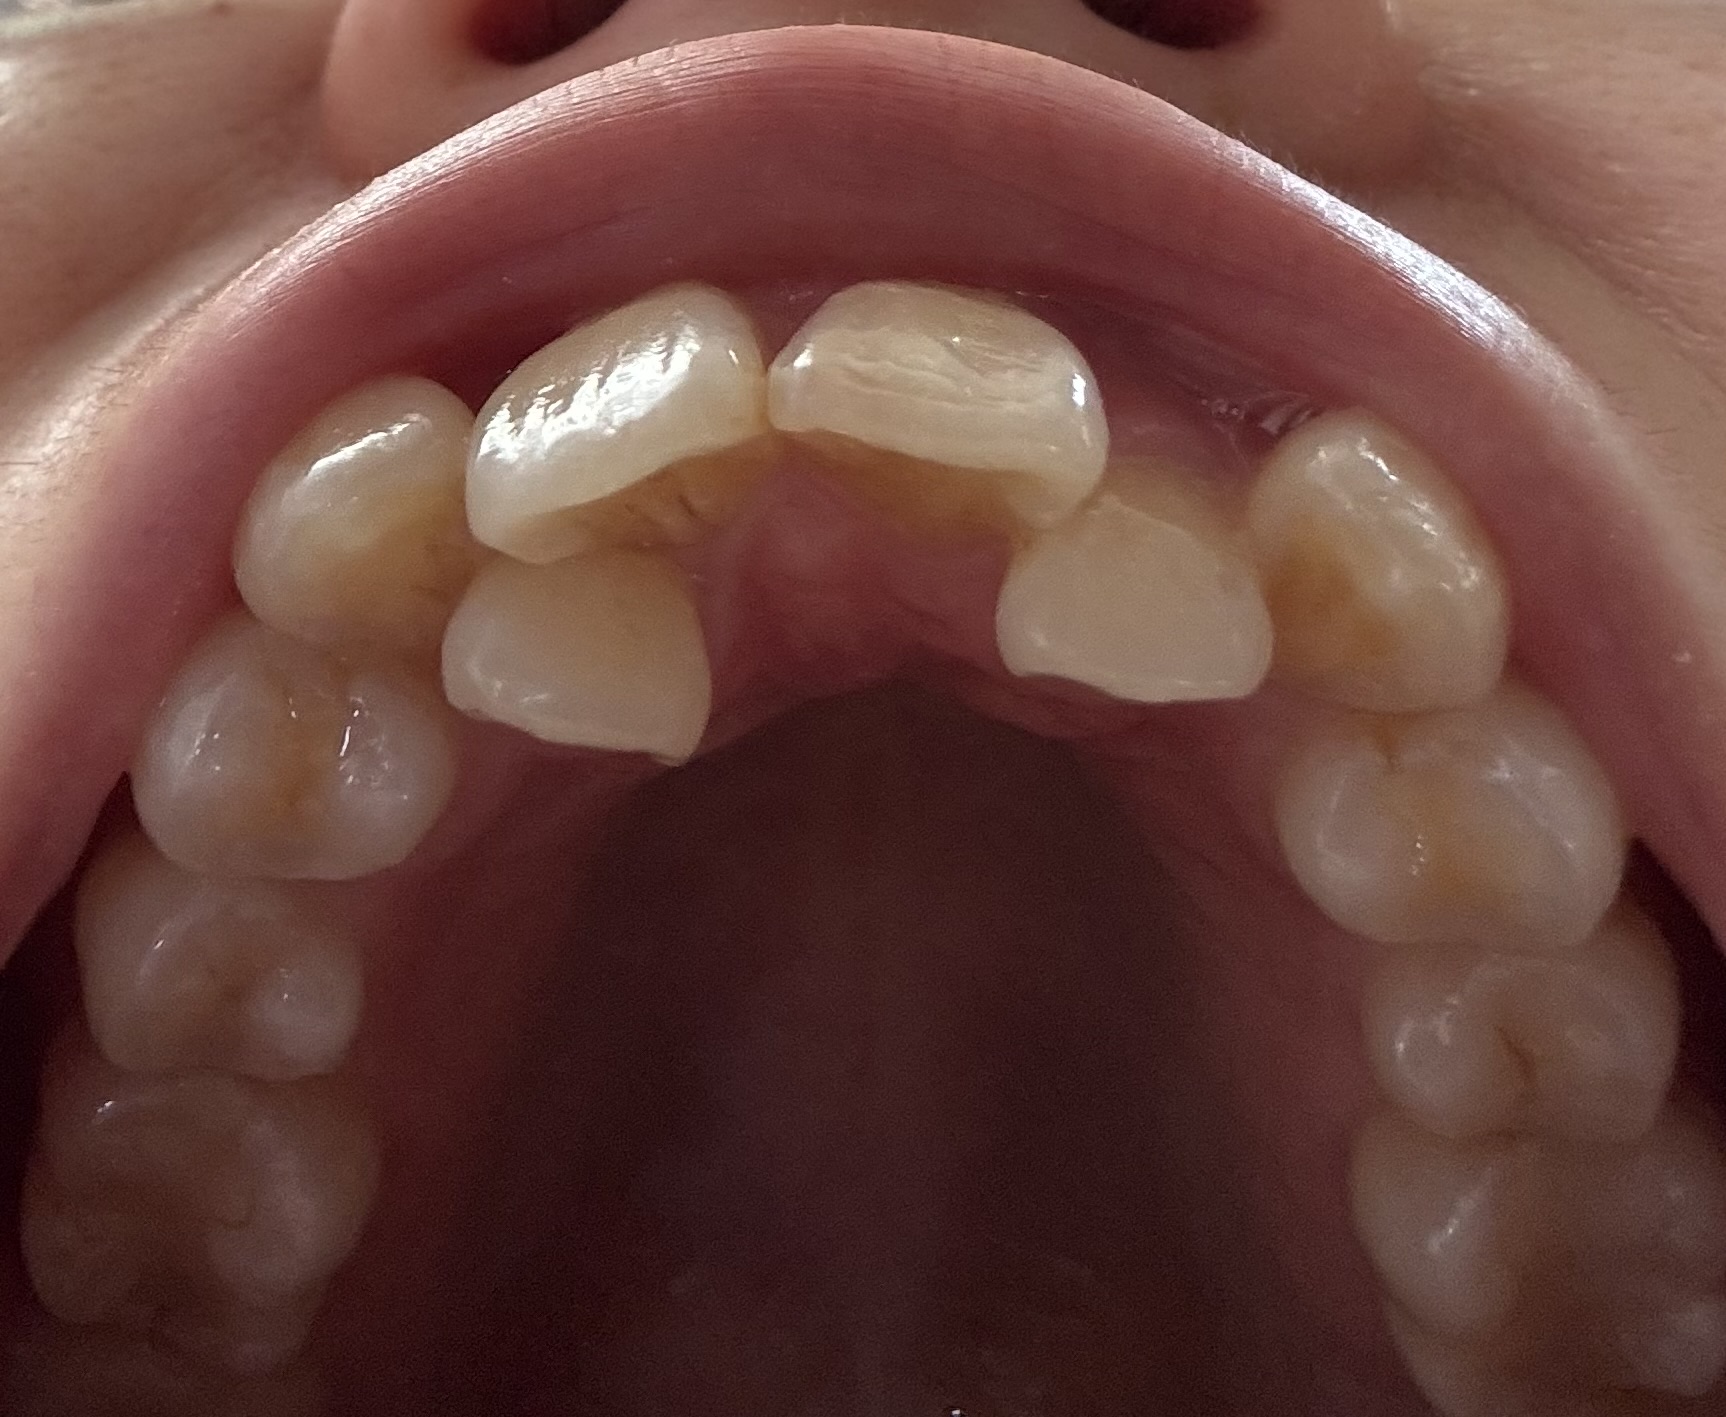

右上は2番を抜歯、左上は4番を抜歯、下に関しては上の様子を見てそのうち片側の4番か前に出ている1番どちらか1本の抜歯になると言われました。

また、歯列矯正を終えた時点で上下とも正中線が左右にズレている事や、下の飛び出している1番を抜歯するという事は一般的なのでしょうか?

写真拝見しました、写真から伺えることは右上2番の抜歯は避けられないように思います、右下1番も抜歯になる可能性は高いように思います。

>下の飛び出している1番を抜歯するという事は一般的なのでしょうか?

一般的ではありませんが私も1番抜歯で治療計画を立てます。

上顎側切歯が口蓋側に転移しており、犬歯と中切歯との間にスペースないという症例は時々拝見することがあります。

なお、下顎の前歯部についていえば、上顎歯列との関係もあるため、場合によっては非抜歯ということも考えられます。